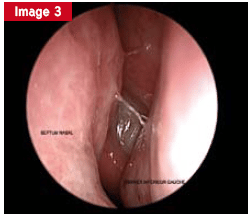

L’endoscopie nasale, incontournable pour l’ORL, fait suite à un examen minutieux et à une rhinoscopie. Elle aide à distinguer un problème de structure d’un trouble fonctionnel. Dans les pathologies fonctionnelles, elle révèle les signes d’inflammation (œdème, pus, croûtes) et leur localisation.

L’endoscopie permet de scruter l’état de la muqueuse, la présence d’œdèmes, de croûtes, ou de sécrétions (séreuses, purulentes, sanglantes). Chaque cavité nasale est explorée avec rigueur : cloison, cornets, voûte, récessus, méats. Il est parfois nécessaire de repousser délicatement le cornet moyen pour accéder au méat moyen, lieu de drainage principal de certains sinus.

La figure illustre un cas d’obstruction nasale unilatérale persistante, liée à un gonflement muriforme visible en endoscopie, révélant un papillome inversé. L’IRM met en évidence l’aspect spécifique de la lésion. Un polype antrochoanal, quant à lui, se manifeste par une obstruction nasale chronique et une rhinorrhée persistante, nécessitant une exérèse complète pour éviter les récidives.

En opposition, la pathologie purulente peut être unilatérale ou bilatérale. La localisation de l’écoulement purulent aide à identifier la source : un écoulement sous le cornet moyen évoque une atteinte du sinus maxillaire, ethmoïde antérieur ou frontal ; du pus visible dans le récessus sphénoïdal oriente vers le sphénoïde ou l’ethmoïde postérieur. Le prélèvement bactériologique n’est utile qu’en cas de chronicité, avec un protocole d’échantillonnage rigoureux.